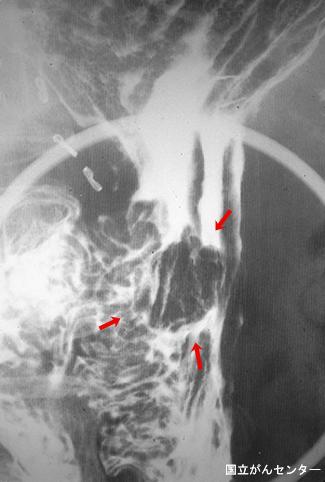

질환(병리주체)의 분류 악성 상피성종양/선암

부위(장기별) 위(부위)/체부

검사방법 X-P

종양의 육안분류 0형(표재형)/I형(I)

종양의 최대경(밀리미터) 15~19

종양의 심달도 m